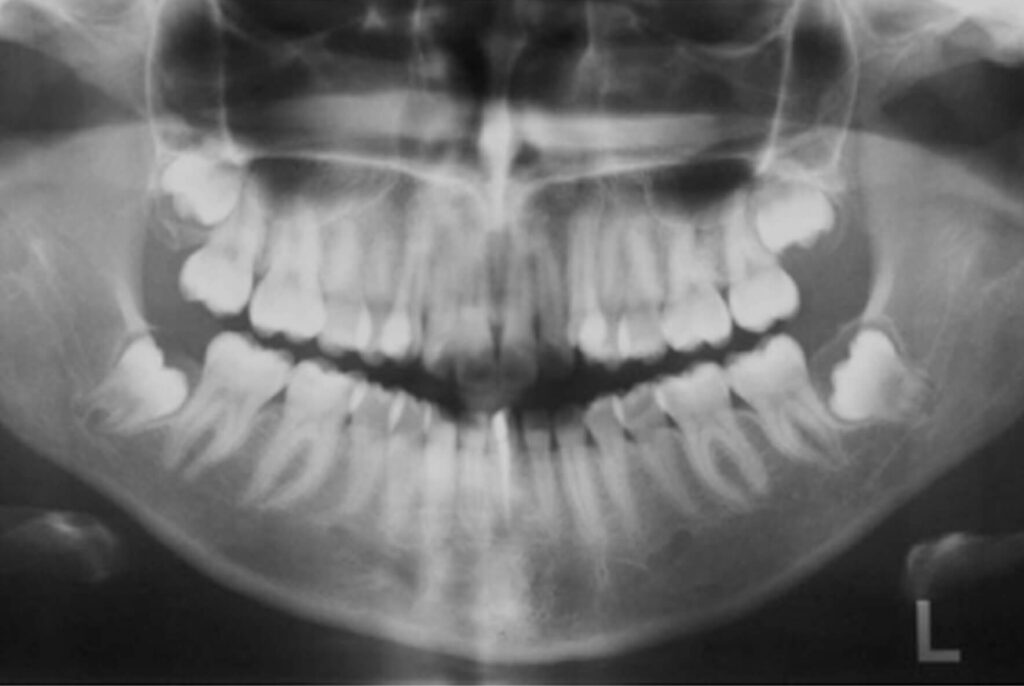

Pela radiografia panorâmica, observou-se a presença de todos os dentes permanentes e estruturas adjacentes com

aspecto de normalidade. Constatou-se a presença de tratamento endodôntico no dente geminado localizado na região

de incisivos centrais inferiores (Figura 3).